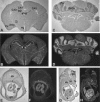

Detailed analyses of 20 patients with sporadic neurofibromatosis type 1 (NF1) microdeletions revealed an unexpected high frequency of somatic mosaicism (8/20 [40%]). This proportion of mosaic deletions is much higher than previously anticipated. Of these deletions, 16 were identified by a screen of unselected patients with NF1. None of the eight patients with mosaic deletions exhibited the mental retardation and facial dysmorphism usually associated with NF1 microdeletions. Our study demonstrates the importance of a general screening for NF1 deletions, regardless of a special phenotype, because of a high estimated number of otherwise undetected mosaic NF1 microdeletions. In patients with mosaicism, the proportion of cells with the deletion was 91%-100% in peripheral leukocytes but was much lower (51%-80%) in buccal smears or peripheral skin fibroblasts. Therefore, the analysis of other tissues than blood is recommended, to exclude mosaicism with normal cells in patients with NF1 microdeletions. Furthermore, our study reveals breakpoint heterogeneity. The classic 1.4-Mb deletion was found in 13 patients. These type I deletions encompass 14 genes and have breakpoints in the NF1 low-copy repeats. However, we identified a second major type of NF1 microdeletion, which spans 1.2 Mb and affects 13 genes. This type II deletion was found in 8 (38%) of 21 patients and is mediated by recombination between the JJAZ1 gene and its pseudogene. The JJAZ1 gene, which is completely deleted in patients with type I NF1 microdeletions and is disrupted in deletions of type II, is highly expressed in brain structures associated with learning and memory. Thus, its haploinsufficiency might contribute to mental impairment in patients with constitutional NF1 microdeletions. Conspicuously, seven of the eight mosaic deletions are of type II, whereas only one was a classic type I deletion. Therefore, the JJAZ1 gene is a preferred target of strand exchange during mitotic nonallelic homologous recombination. Although type I NF1 microdeletions occur by interchromosomal recombination during meiosis, our findings imply that type II deletions are mediated by intrachromosomal recombination during mitosis. Thus, NF1 microdeletions acquired during mitotic cell divisions differ from those occurring in meiosis and are caused by different mechanisms.